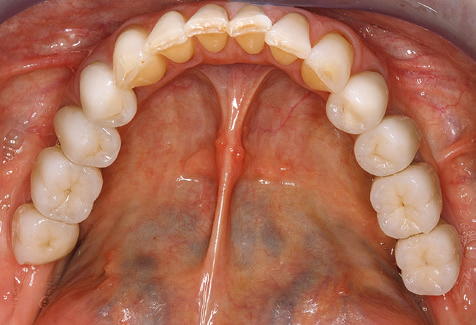

Fig. 9: The accessible implant and tooth surfaces are polished with polishing cups and suitable polishing compounds. – Fig. 10: Repeat instruction in the use of appropriate aids for oral hygiene at home should also form part of SPT. – Fig. 11a and b: Clinical situation 12 years after insertion of the prosthetic restoration. During this period, only a veneering ceramic fracture on tooth 47 and the requirement for endodontic treatment of tooth 12 were observed. All restorations are still functioning as intended.

Summary

Standardised and regular risk-adapted care in the scope of SPT is the key to treatment success for the clinical long-term success in periodontically compromised patients. This is particularly true for patients fitted with implants following successfully completed periodontal treatment (Fig. 11a and b).